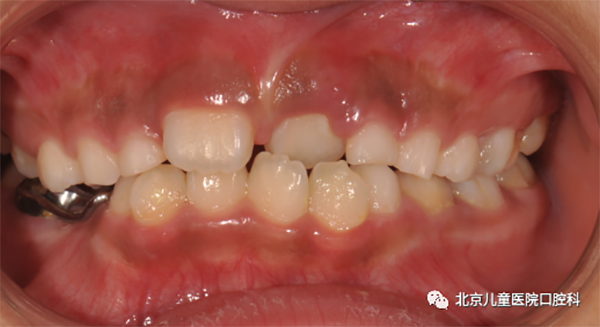

图1 埋伏牙

1. 多生牙或埋伏牙

应拔除多生牙或埋伏牙,并利用正畸手段使正中间隙得以闭合。